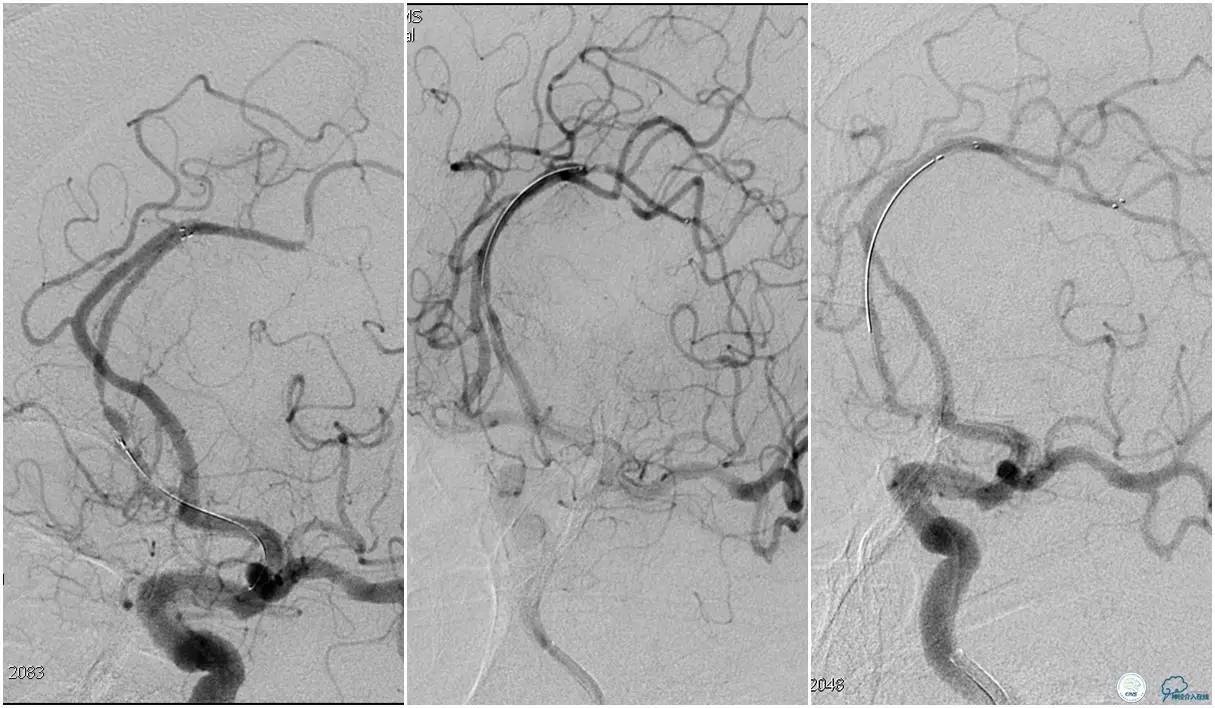

双侧大脑前动脉完全显影,TICI 3级,TOR 261min。

术后头颅CT复查。

术后复查头颅CTA。

术后复查头颅MRI。

术后第二天患者意识清,言语清,右上肢肌力1级,右下肢肌力3级,左上肢肌力5级,左下肢3级。

术后90天随访右上肢肌力3级,左上肢肌力5级,双下肢肌力4级,mRS评分3分。